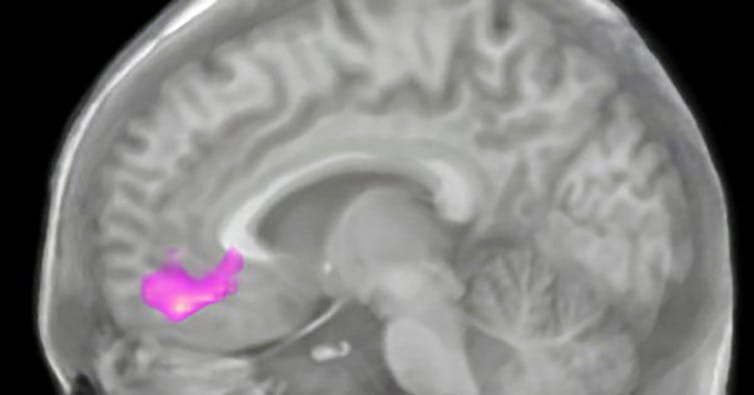

Deep in the front part of your brain, the ventromedial prefrontal cortex helps process risk and reward. Christina Karns, CC BY-ND

It turns out that the neural connection between gratitude and giving is very deep, both literally and figuratively. A region deep in the frontal lobe of the brain, called the ventromedial prefrontal cortex, is key to supporting both. Anatomically, this region is wired up to be a hub for processing the value of risk and reward; it’s richly connected to even deeper brain regions that provide a kick of pleasurable neurochemicals in the right circumstances. It holds abstract representations of the inner and outer world that help with complex reasoning, one’s representation of oneself and even social processing.

The pink in these scans shows the region that responded more to giving after practicing gratitude for three weeks.